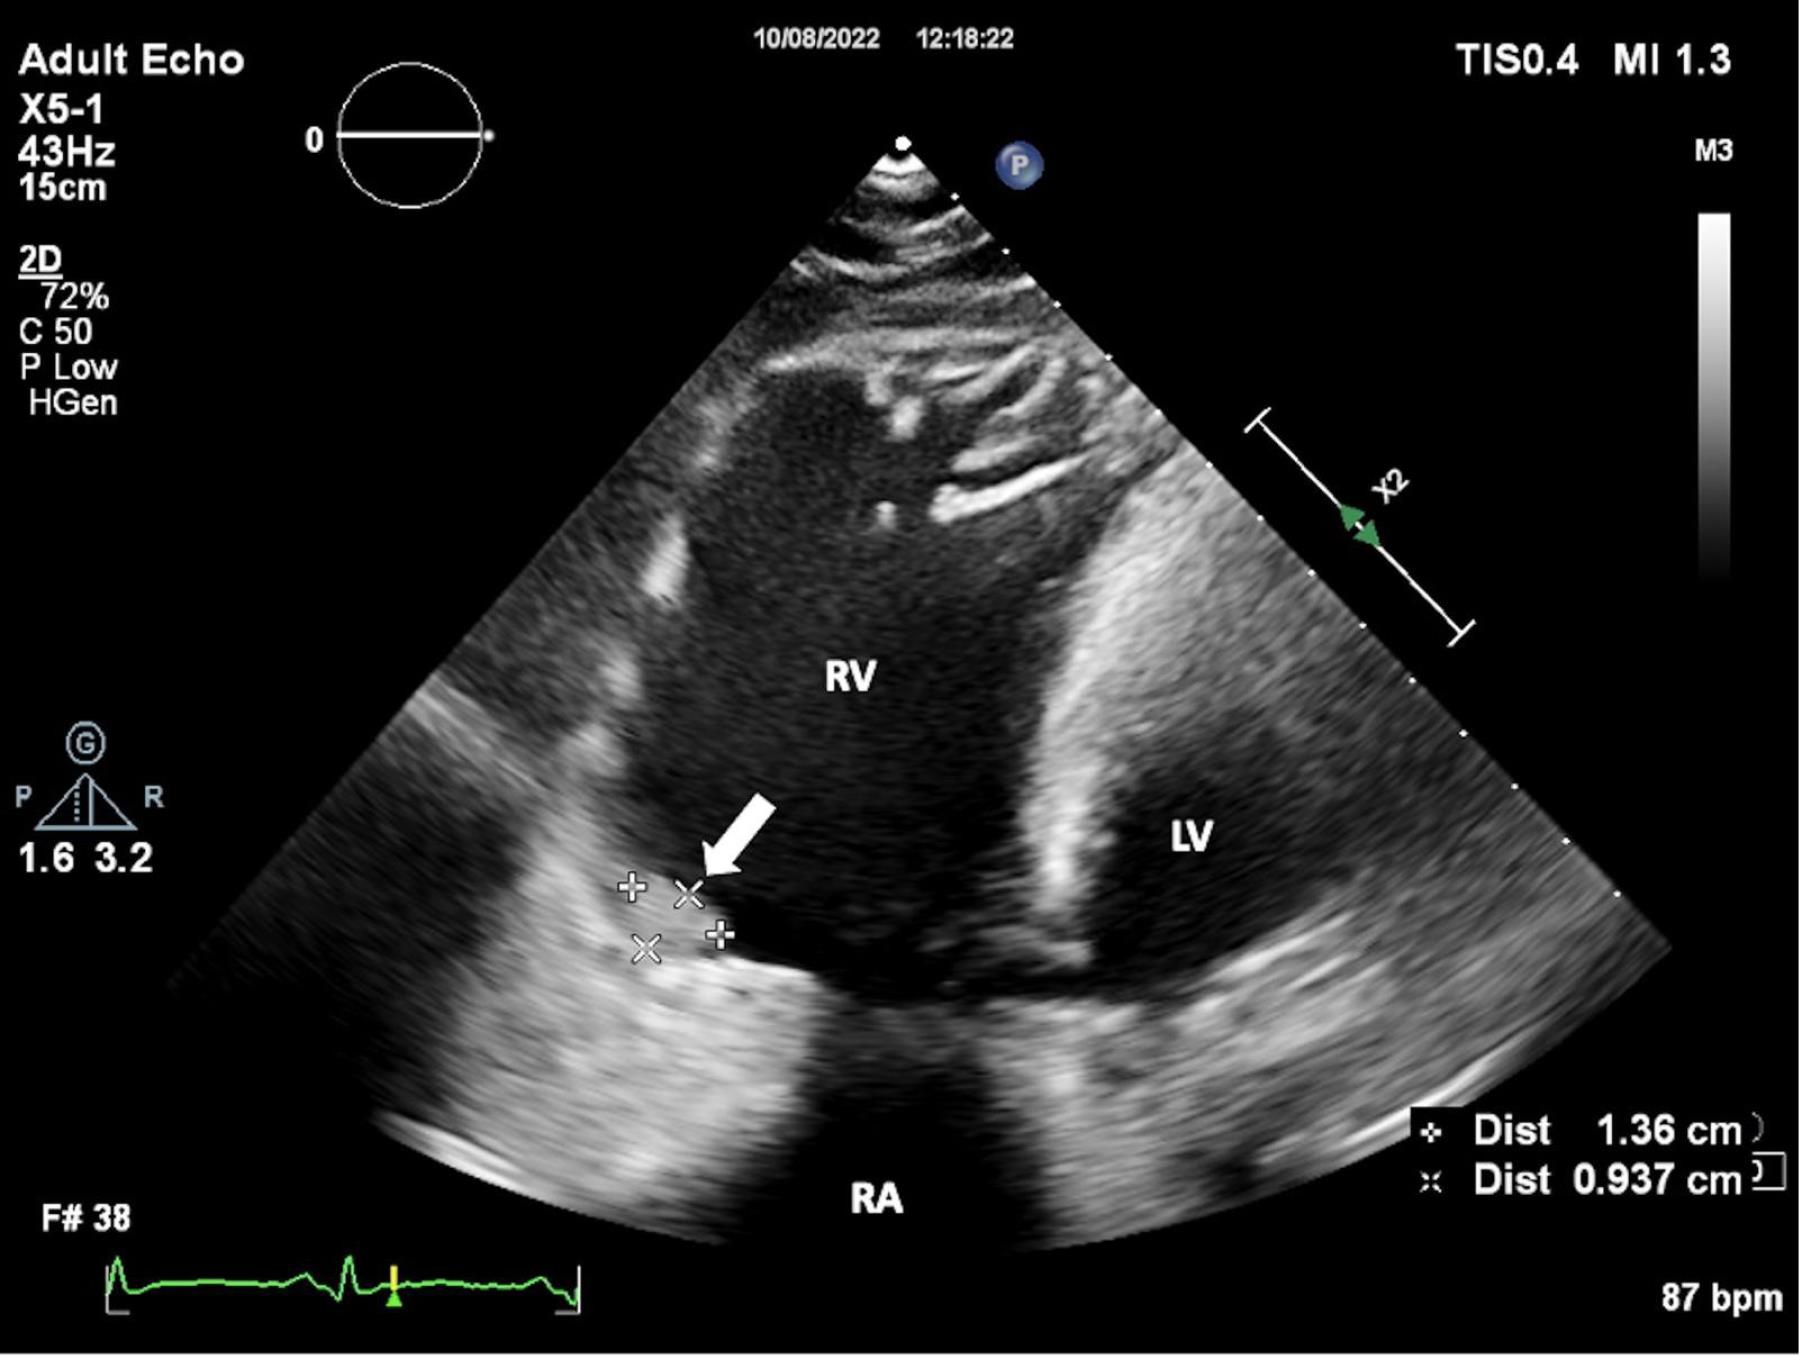

A 24-year-old female patient was admitted to our tertiary center with chest pain. She had no family history of cardiac disease or sudden cardiac death. Her electrocardiogram (ECG) was sinus rhythm and T wave negativity was detected in leads V1-5. (Figure 1) TTE showed a slight decrease in LV ejection fraction as 45%, prominently dilated right heart chambers, decreased RV functions (TAPSE: 11, tricuspid annular peak systolic velocity: 7.7), severe tricuspid regurgitation (Supplementary file 1, Video 1). Additionally, an image of 13.6 x 9.3 mm, hyperechoic, consistent with thrombus was observed in the lateral wall of the RV (Figure 2). No thromboembolism was reported in the pulmonary CTA. The patient underwent cardiac magnetic resonance imaging (CMR) for morphological and functional assessment of the heart. The CMR images showed enlarged RV and right atrium, severe hypokinesia of the RV, dyskinesia in the free wall of RV and paradoxical movement in interventricular septum, and wall irregularity in both ventricles (Figure 3). In the cardiac MRI, The LV ejection fraction was 49%, the LV end-systolic volume was 143 mL, end-diastolic volume was 73 mL, and stroke output was 60 mL. The LV end-diastolic volume index (LVEDVI) was 74 mL/m2, the LV end-systolic volume index (LVESVI) was 42 mL/m2. The RV ejection fraction was 20%, the RV end-systolic volume was 430 mL, end-diastolic volume was 343 mL, and stroke output was 87 mL. The RV end-diastolic volume index (RVEDVI) was 221 mL/m2, the RV end-systolic volume index (RVESVI) was 176 mL/m2. The late gadolinium images depicted diffuse enhancement in the right ventricular free wall and inferior wall. The left ventricular inferior septum showed midwall enhancement. A nodular mass was noted on the lateral wall of RV in the vicinity of the tricuspid valve which did not uptake gadolinium and was compatible with thrombus (Figure 4). As a result of these findings, genetic analysis was performed with a high suspicion of arrhythmogenic cardiomyopathy. The genetic analysis revealed a homozygous nonsense mutation in the desmoglein-2 gene, proven to be pathogenic in databases, and the diagnosis of arrhythmogenic cardiomyopathy was definitively confirmed with the findings from TTE, ECG, CMR, and genetic tests, which are part of the aforementioned Padua criteria.

Figure 2.

Wall Irregularity of the Right Ventricle. Transthoracic echocardiography (TTE) shows the wall irregularity of the right ventricle. FIGUR LEGEND: TTE: Transthoracic Echocardiography, RA: Right Atrium, RV: Right Ventricle, LV: Left Ventricle.

Video 1: The video shows biventricular dysfunction, marked right heart dilatation, severe tricuspid regurgitation, and a thrombus in the lateral wall of the right ventricle as demonstrated by TTE. (TTE: transthoracic echocardiography)